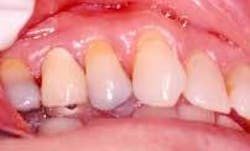

Disease masking is a term that has been applied to describe the appearance of the gingiva associated with chronic smokers.23 Typically, the diseased tissues of smokers tend to have a firmer appearance and less bleeding compared to that of nonsmokers. The term disease masking is used because the vasoconstrictive properties of tobacco smoke hide the inflammatory and destructive changes occurring within the periodontium (See Figures 1a and 1b). The periodontal tissues are compromised by the initial vasoconstriction, resulting in decreased blood flow to the gingiva. This masks the normal early signs of periodontal problems by decreasing gingival inflammation, erythema, and bleeding despite the presence of the disease.